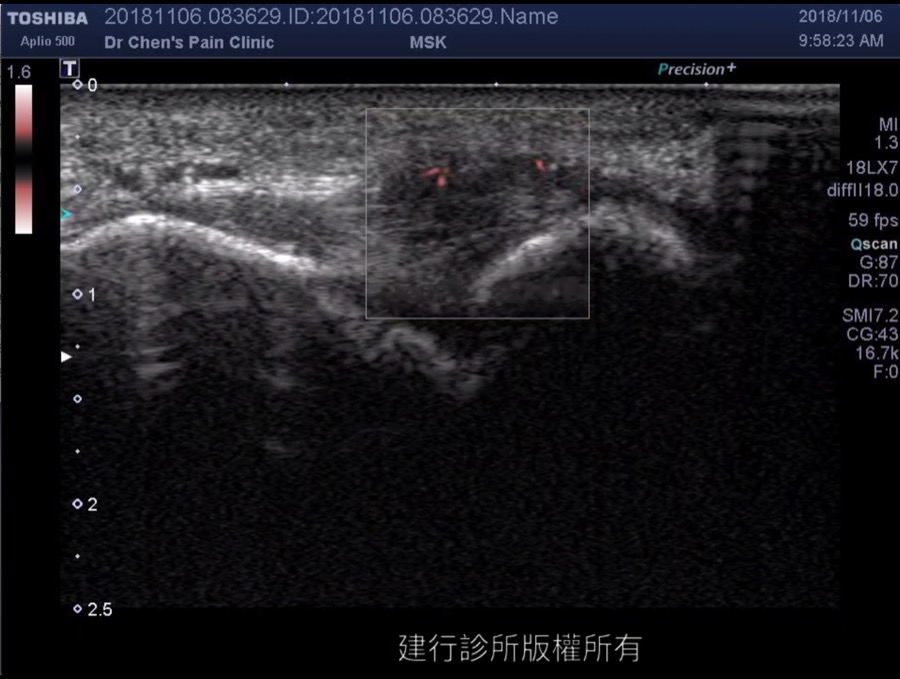

踝關節影像

為何麼腳踝扭傷後一直都不會完全好